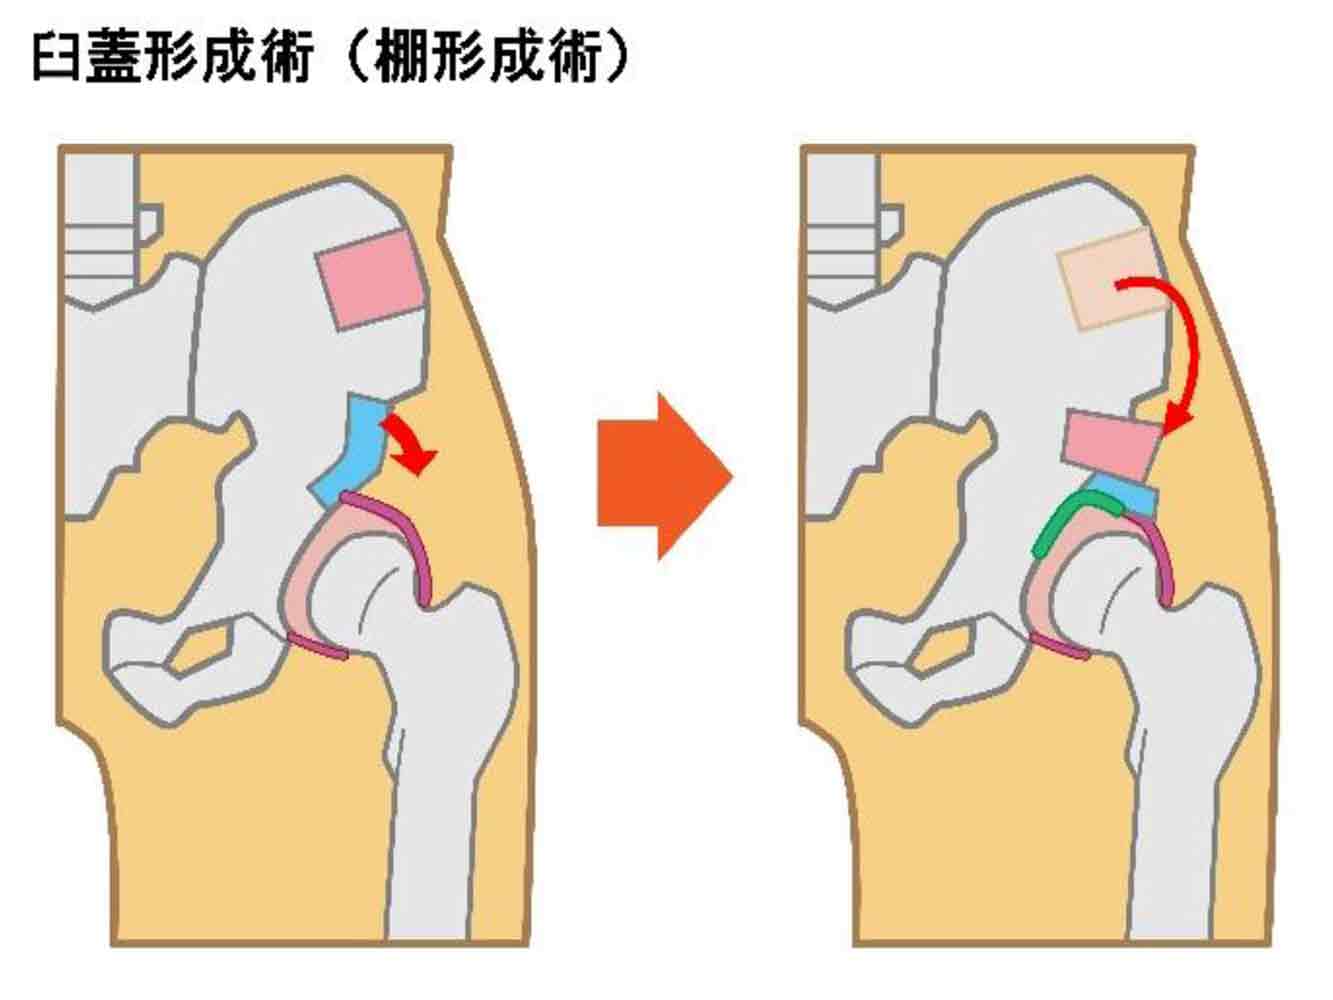

骨切り術/棚形成術

主に変形性股関節症の初期段階において適応される術式で、骨の一部を切除して形状を修正する手術のことを指します。骨の癒合までにある程度時間がかかるため、入院期間、リハビリ期間ともに人工股関節置換術より長くなるのが難点です。